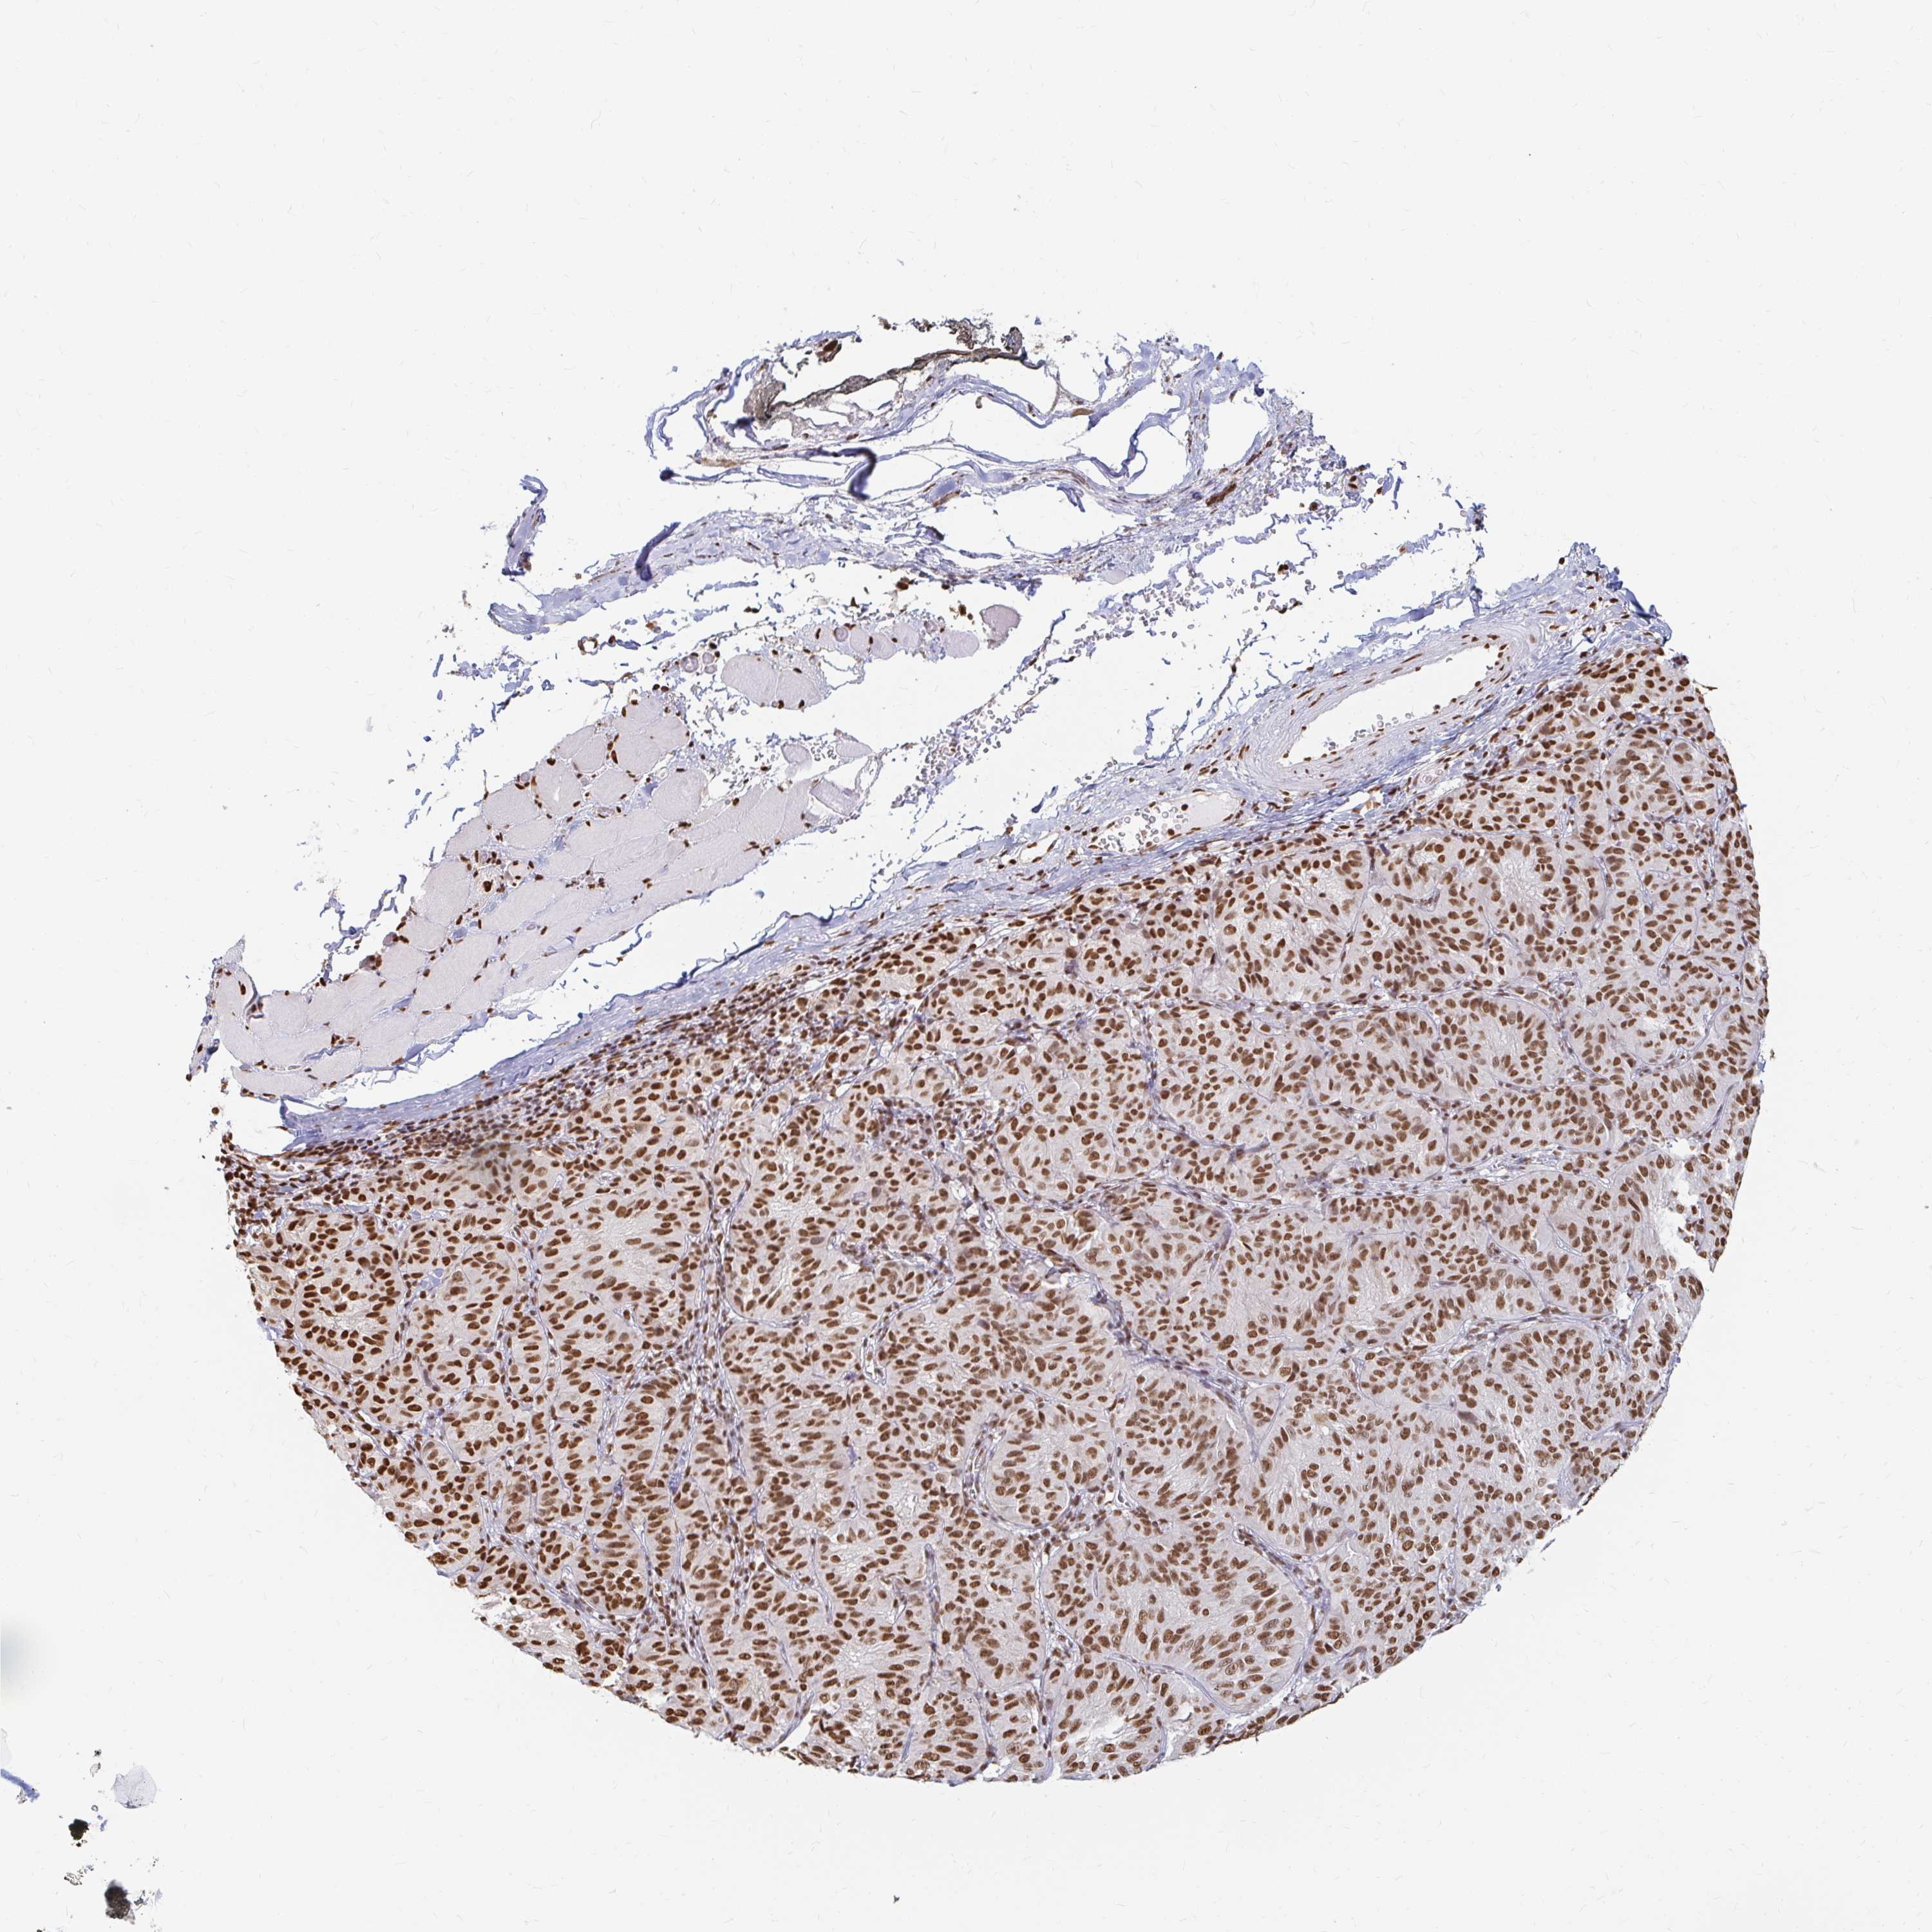

MELANOMA - Protein expressioni

A mouse-over function shows sample information and annotation data. Click on an image to view it in a full screen mode. Samples can be filtered based on level of antibody staining by selecting one or several of the following categories: high, medium, low and not detected. The assay and annotation is described here.

Note that samples used for immunohistochemistry by the Human Protein Atlas do not correspond to samples in the TCGA dataset.

Antibody stainingi

Antibody staining in the annotated cell types in the current human tissue is reported as not detected, low, medium, or high, based on conventional immunohistochemistry profiling in selected tissues. This score is based on the combination of the staining intensity and fraction of stained cells.

Each image is clickable and will lead to virtual microscopy that enables deeper exploration of all samples and also displays staining intensity scores, fraction scores and subcellular localization as well as patient and tissue information for each sample.

Antibody HPA041057

Antibody HPA058707

Antibody CAB011532

Staining

High

Medium

Low

Not detected

Intensity

Strong

Moderate

Weak

Negative

Quantity

>75%

75%-25%

<25%

None

Location

Nuclear

Cytoplasmic/membranous

Cytoplasmic/membranous,nuclear

Malignant melanoma, NOS

Malignant melanoma, Metastatic site